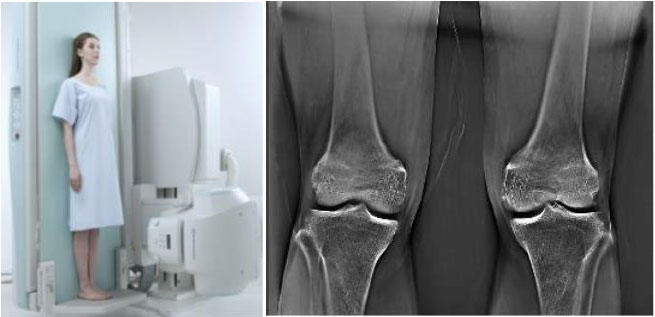

通过一次扫描即可进行多层面的断层图像重建,相比常规 CT,用时更少,剂量更低。它还可以大限度地减少金属伪影,并且可以在倾斜的床面上进行扫描,从而实现负重诊断,因此断层融合技术在骨科中非常受欢迎。